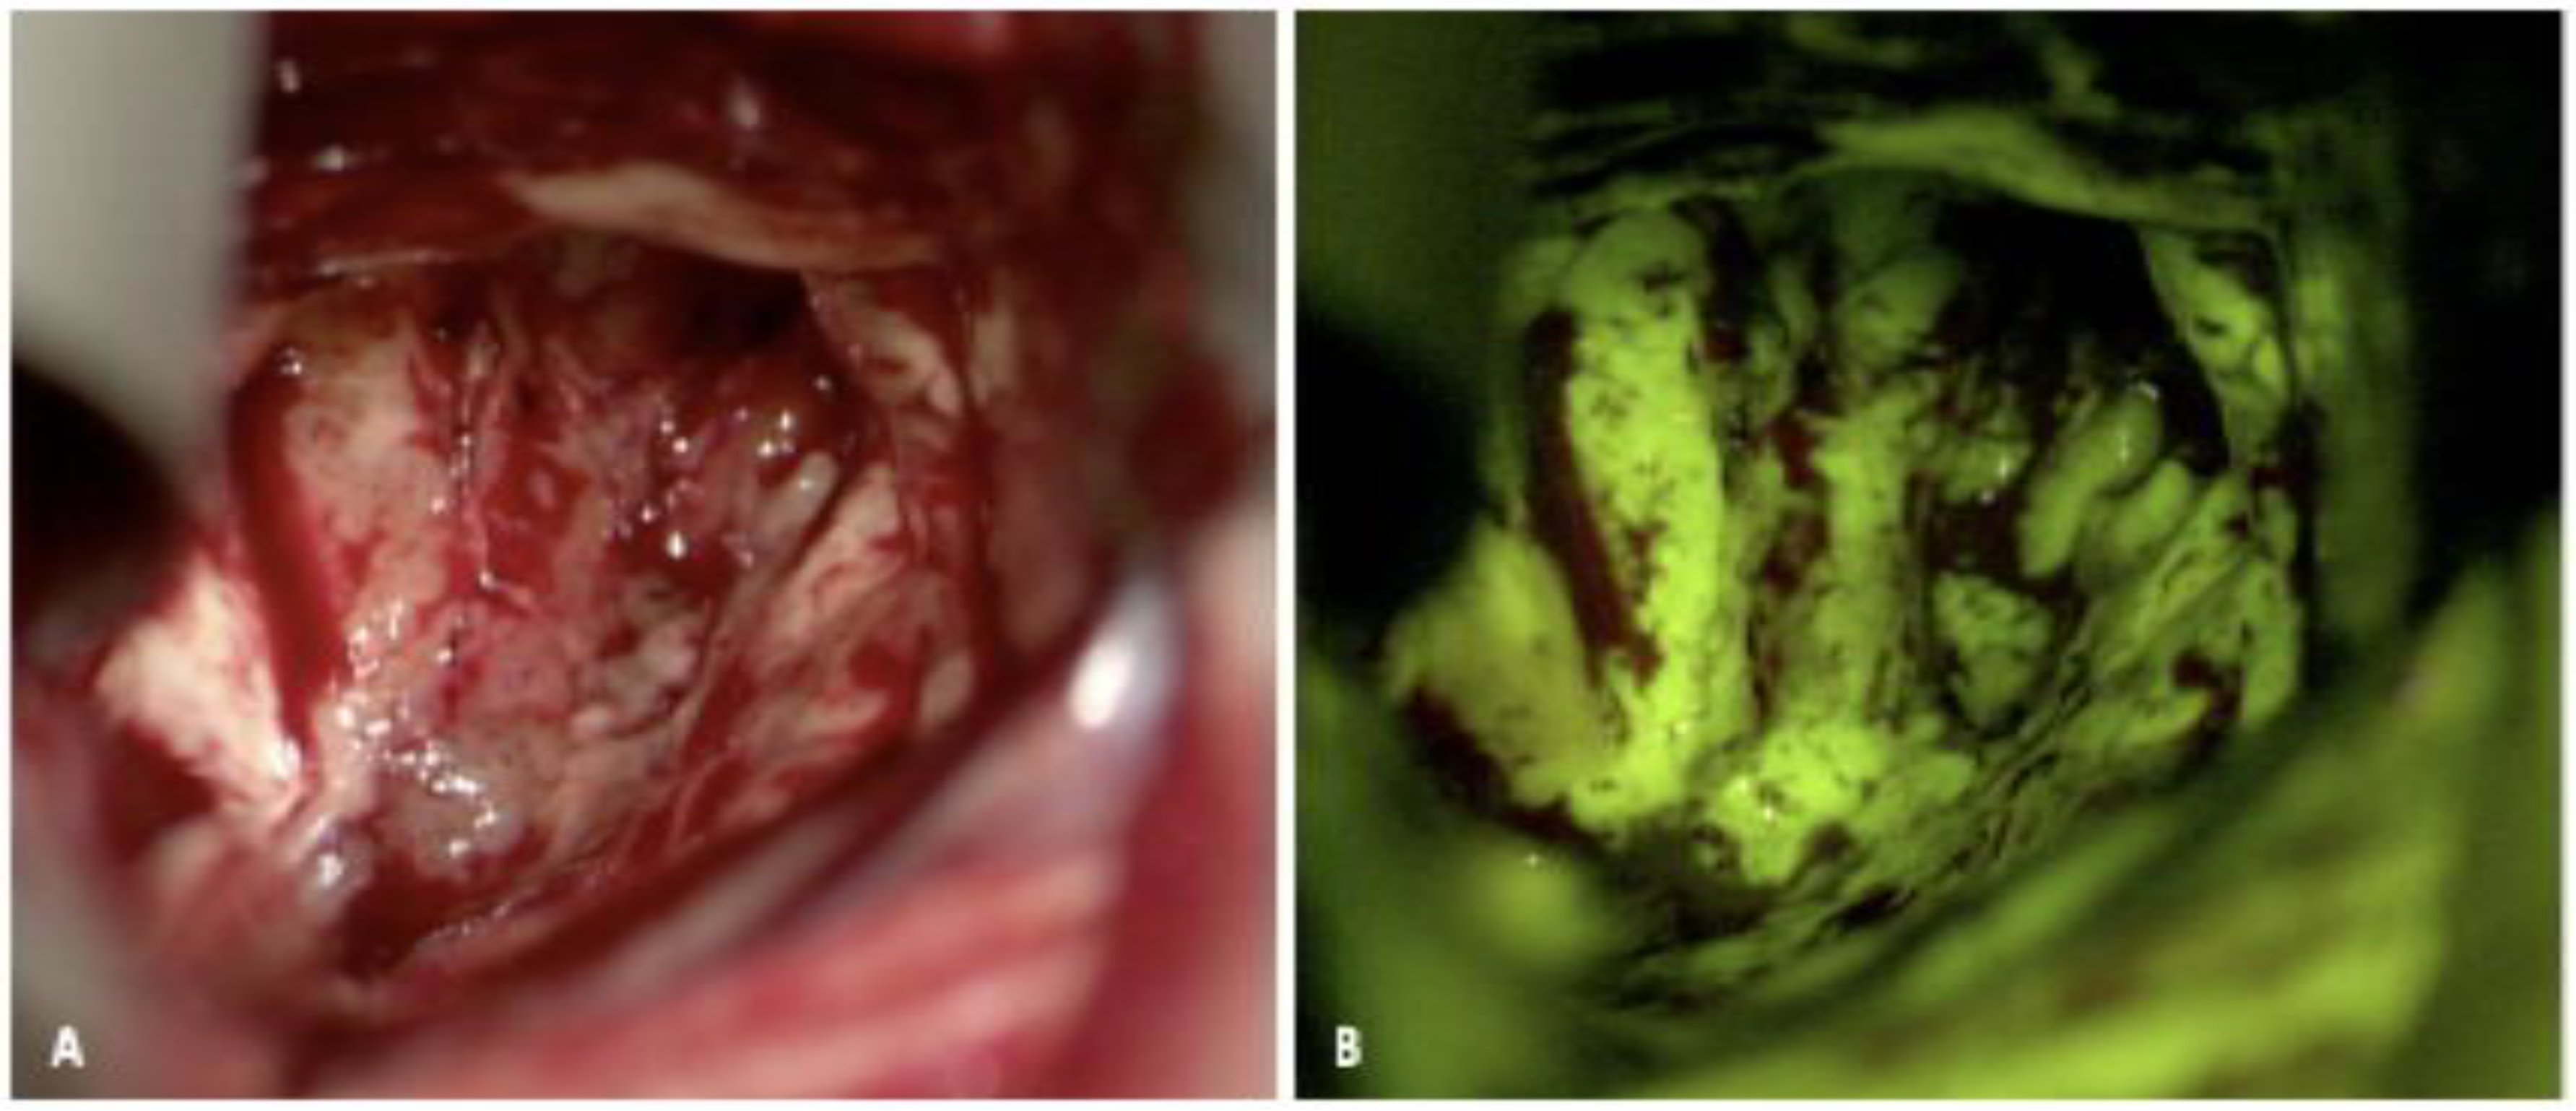

2.2. Fluorescein

2.2.1. Fluorescein: Background and Mechanism of Action

2.2.2. Fluorescein: Evidence for Use

2.2.3. Fluorescein: Limitations